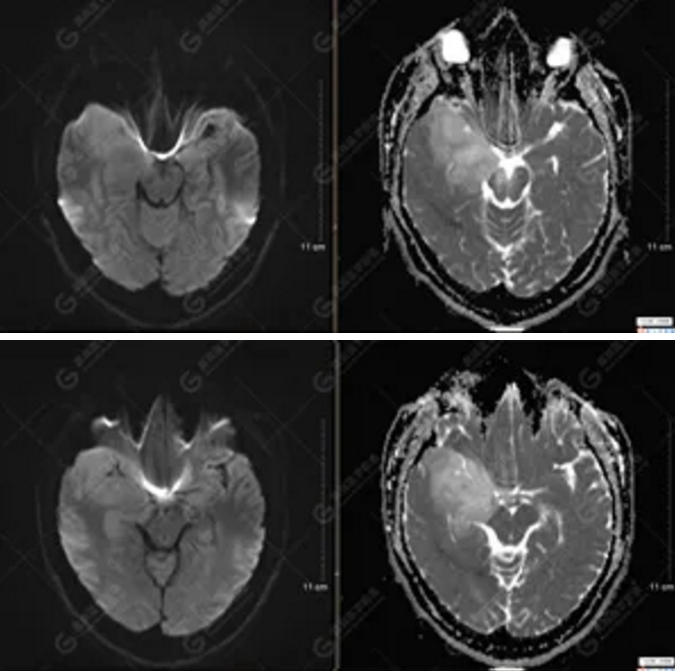

MR影像圖

【MRI平掃及增強(qiáng)檢查所見(jiàn)】右側(cè)額顳島葉、右側(cè)海馬及右側(cè)基底節(jié)區(qū)見(jiàn)一團(tuán)塊狀異常信號(hào)影,累及右側(cè)下丘腦及視交叉,大小約5.1cm×4.5cm×4.3cm,呈長(zhǎng)T1長(zhǎng)T2信號(hào),F(xiàn)LAIR序列呈等、稍高信號(hào),DWI序列呈稍高信號(hào),ADC圖高信號(hào),增強(qiáng)后無(wú)明顯強(qiáng)化;病灶周?chē)?jiàn)片狀長(zhǎng)T1長(zhǎng)T2水腫信號(hào)影,F(xiàn)LAIR序列呈高信號(hào),病灶內(nèi)見(jiàn)右側(cè)大腦中動(dòng)脈穿行。余腦實(shí)質(zhì)內(nèi)未見(jiàn)局灶性信號(hào)異常,增強(qiáng)后未見(jiàn)異常強(qiáng)化。右側(cè)側(cè)腦室輕度受壓,余腦室、腦池大小、形態(tài)均正常,中線(xiàn)結(jié)構(gòu)居中